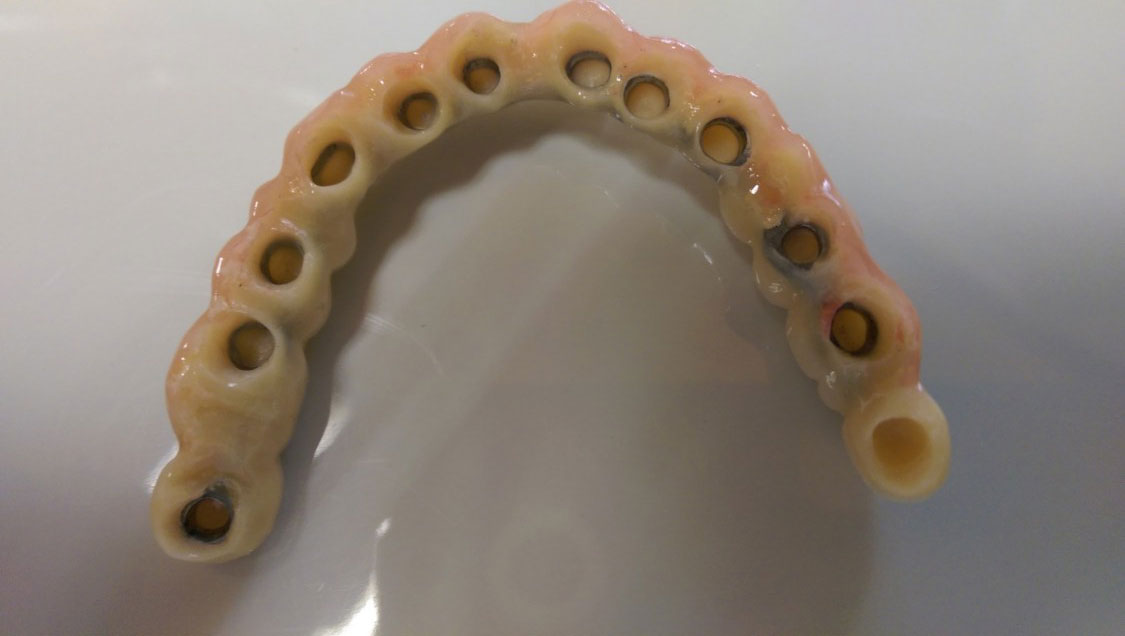

Sikerét mindenekelőtt a gyorsaságának köszönheti, hiszen a mai rohanó világban kinek van ideje, kedve fogatlanul otthon ülni heteket, hónapokat a fogpótlásra várva? Az Ihde implantációs eljárás során a páciens azonnal, de legkésőbb 72 óra múlva egy rögzített (tehát nem mozgó, nem kivehető) pótlással hagyja el a rendelőt. Ez az egyedülállóan gyors eljárás annak köszönhető, hogy azonnal tudunk implantálni szinte bárhova, akár foghúzás után is, továbbá a művelet nem jár nagy feltárásokkal, nincs szükség csontbeültetésre, így a gyógyulás folyamata is nagyon gyors és a beültetés technikájának köszönhetően maximum 72 óra múlva a korona is feltehető. Tehát ennyi idő alatt foga lesz a betegnek és az implantátum azonnal terhelhetővé is válik.

Természetesen, az Ihde Azonnal Terhelhető Implantátum Rendszer alkalmazása speciális szaktudást igényel, így elengedhetetlen az orvosok gondos és folyamatos képzése. Ez, illetve a kiváló minőségű svájci alapanyagok és a sok évtizedes, precíz, innovatív gyártási technológia együttese adja, hogy a cég kiemelkedően magas (98,2%-os) sikert ér el, az Ihde implantátumok bent maradásának mérésekor.